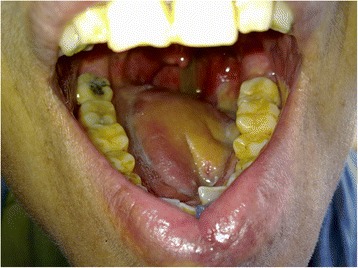

Fig. 1.

Preoperative view of large left sided tongue squamous cell carcinoma